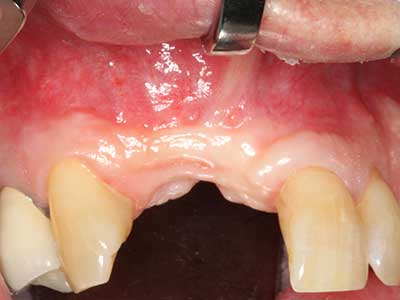

Marginal periodontal diseases are the main reason for extractions in advanced age. These diseases are primarily caused by bacterial colonization of the gingival pocket, which causes inflammation followed by loss of the periodontium. The formation of subgingival biofilms and concrements is a significant aetiological factor for marginal bone atrophy, so their removal is an important part of the treatment (Drisko 2014, Plessas 2014).

Initial and surgical treatment phases are differentiated in the treatment of marginal periodontitis. In addition to instruction in oral hygiene and motivating patients, both phases should include adequate cleaning of the root surface. In the regenerative setting an open access is generally preferred. The root surface can be cleaned by piezosurgery using special attachments, where instruments with different curvatures are used to reach areas that are difficult to access, such as furcations. The integrated irrigation in the system flushes the detached concrements and bacteria out of the pocket. Specialized systems such as the Piezomed also include application feedback to minimize the ablation of hard dental substance. The greater the pressure on the periodontal attachment the greater the reduction in the amount of ablation.